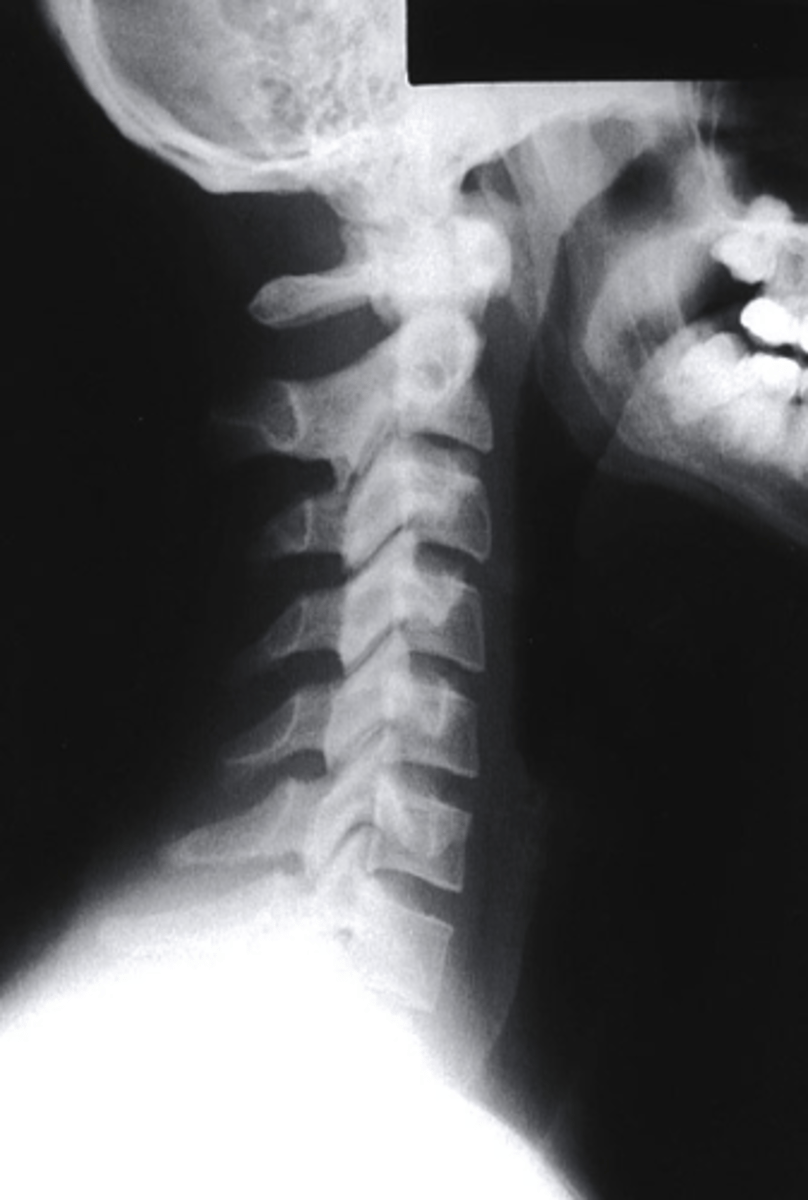

Lateral

which view is this?

a. Lateral

b. Oblique

c. PA

d. AP

what can be identified on a lateral view of the C spine?

-arches of C1

-Dens

-vertebral bodies of C2-C7

-articular pillars and lamina

-IVD spaces from C2-C3 through C6-C7

-spinous processes

-transverse processes

-facet joint surfaces